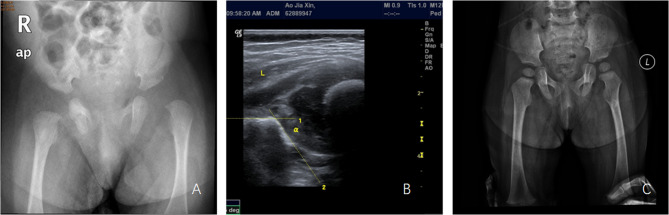

Outcome of infantile septic arthritis of the hip joint: A two-children medical center's experience.

期刊介绍: BMC Musculoskeletal Disorders is an open access, peer-reviewed journal that considers articles on all aspects of the prevention, diagnosis and management of musculoskeletal disorders, as well as related molecular genetics, pathophysiology, and epidemiology. The scope of the Journal covers research into rheumatic diseases where the primary focus relates specifically to a component(s) of the musculoskeletal system.